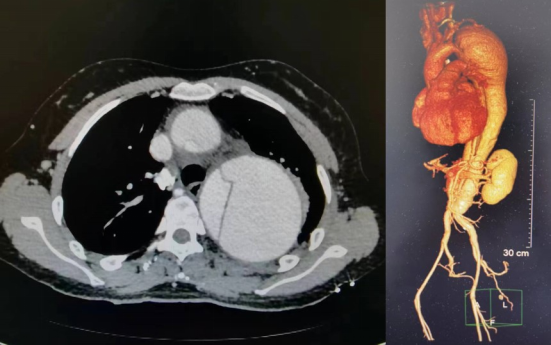

患者术前胸腹主动脉CTA检查结果显示夹层累及范围大、胸降及腹主动脉巨大夹层动脉瘤形成